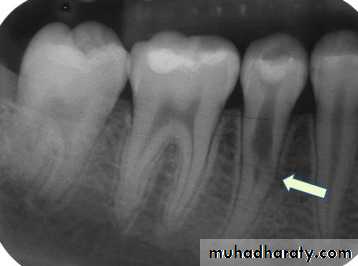

Internal (Intracanal) Resorption

The pulp is transformed into a vascularized inflammatory tissue with dentinoclastic activity; this condition leads to the resorption of the dentinal walls, advancing from its center to the peripheryMost cases of intracanal resorption are asymptomatic. Advanced internal resorption involving the pulp chamber is often associated with pink spots in the crown.

Teeth with intracanal resorptive lesions usually respond within normal limits to pulpal and periapical tests.

Radiographs reveal presence of radiolucency with irregular enlargement of the root canal compartment

Immediate removal of the inflamed tissue and completion of root canal treatment are recommended; these lesions tend to be progressive and eventually perforate to the lateral periodontium.